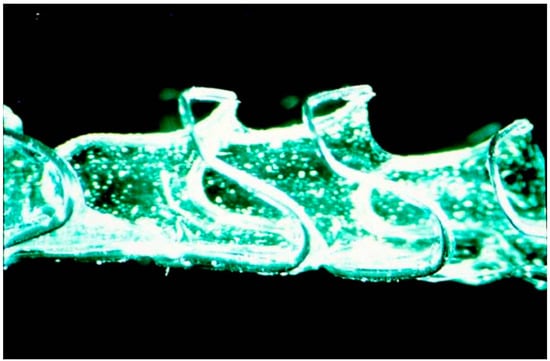

| Materials | Polyglycoside (knitted poly-l-lactic acid monofilaments) | Polydioxanone (a semicrystalline, degradable polymer) |

| Bioabsorption period | 3–6 months | 2–3 months |

| Length and diameter | Designed according to esophageal lesion | Size: 18, 20, 23, 25 mm Length: 60, 80, 100, 135 mm |

| Setting | Fitted over an endoscope | Delivery system |

| Other features | One end is reduced to a diameter of 5 mm by tying with silk sutures | Manual loading is needed |